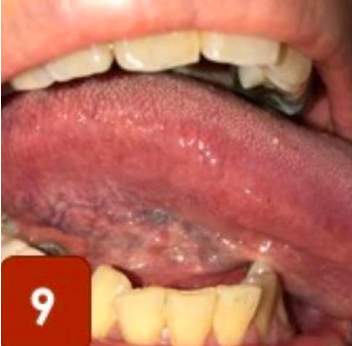

7. Julurkan lidah, dan naikkan lidah ke atas lalu amati area bawah lidah dan dasar mulut

9. Julurkan lidah dan miringkan lidah ke kiri lalu amati pinggir lidah kanan

Pemeriksaan ini dapat di lakukan satu kali dalam bulan. Dan yang harus di perhatikan dalam SAMURI ini adalah perubahan warna, bentuk dan kekenyalan pada rongga mulut, ada atau tidaknya benjolan pada rongga mulut serta adanya rasa sakit pada rongga mulut.